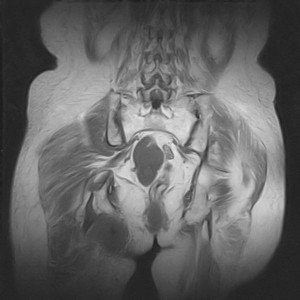

图像太差了 1、右侧臀肌旁脓肿? 建议增强 2、左侧股骨头坏死并半脱位

1、左侧股骨头坏死并髋关节半脱位;

2、右侧臀肌感染,(可能褥疮所致)